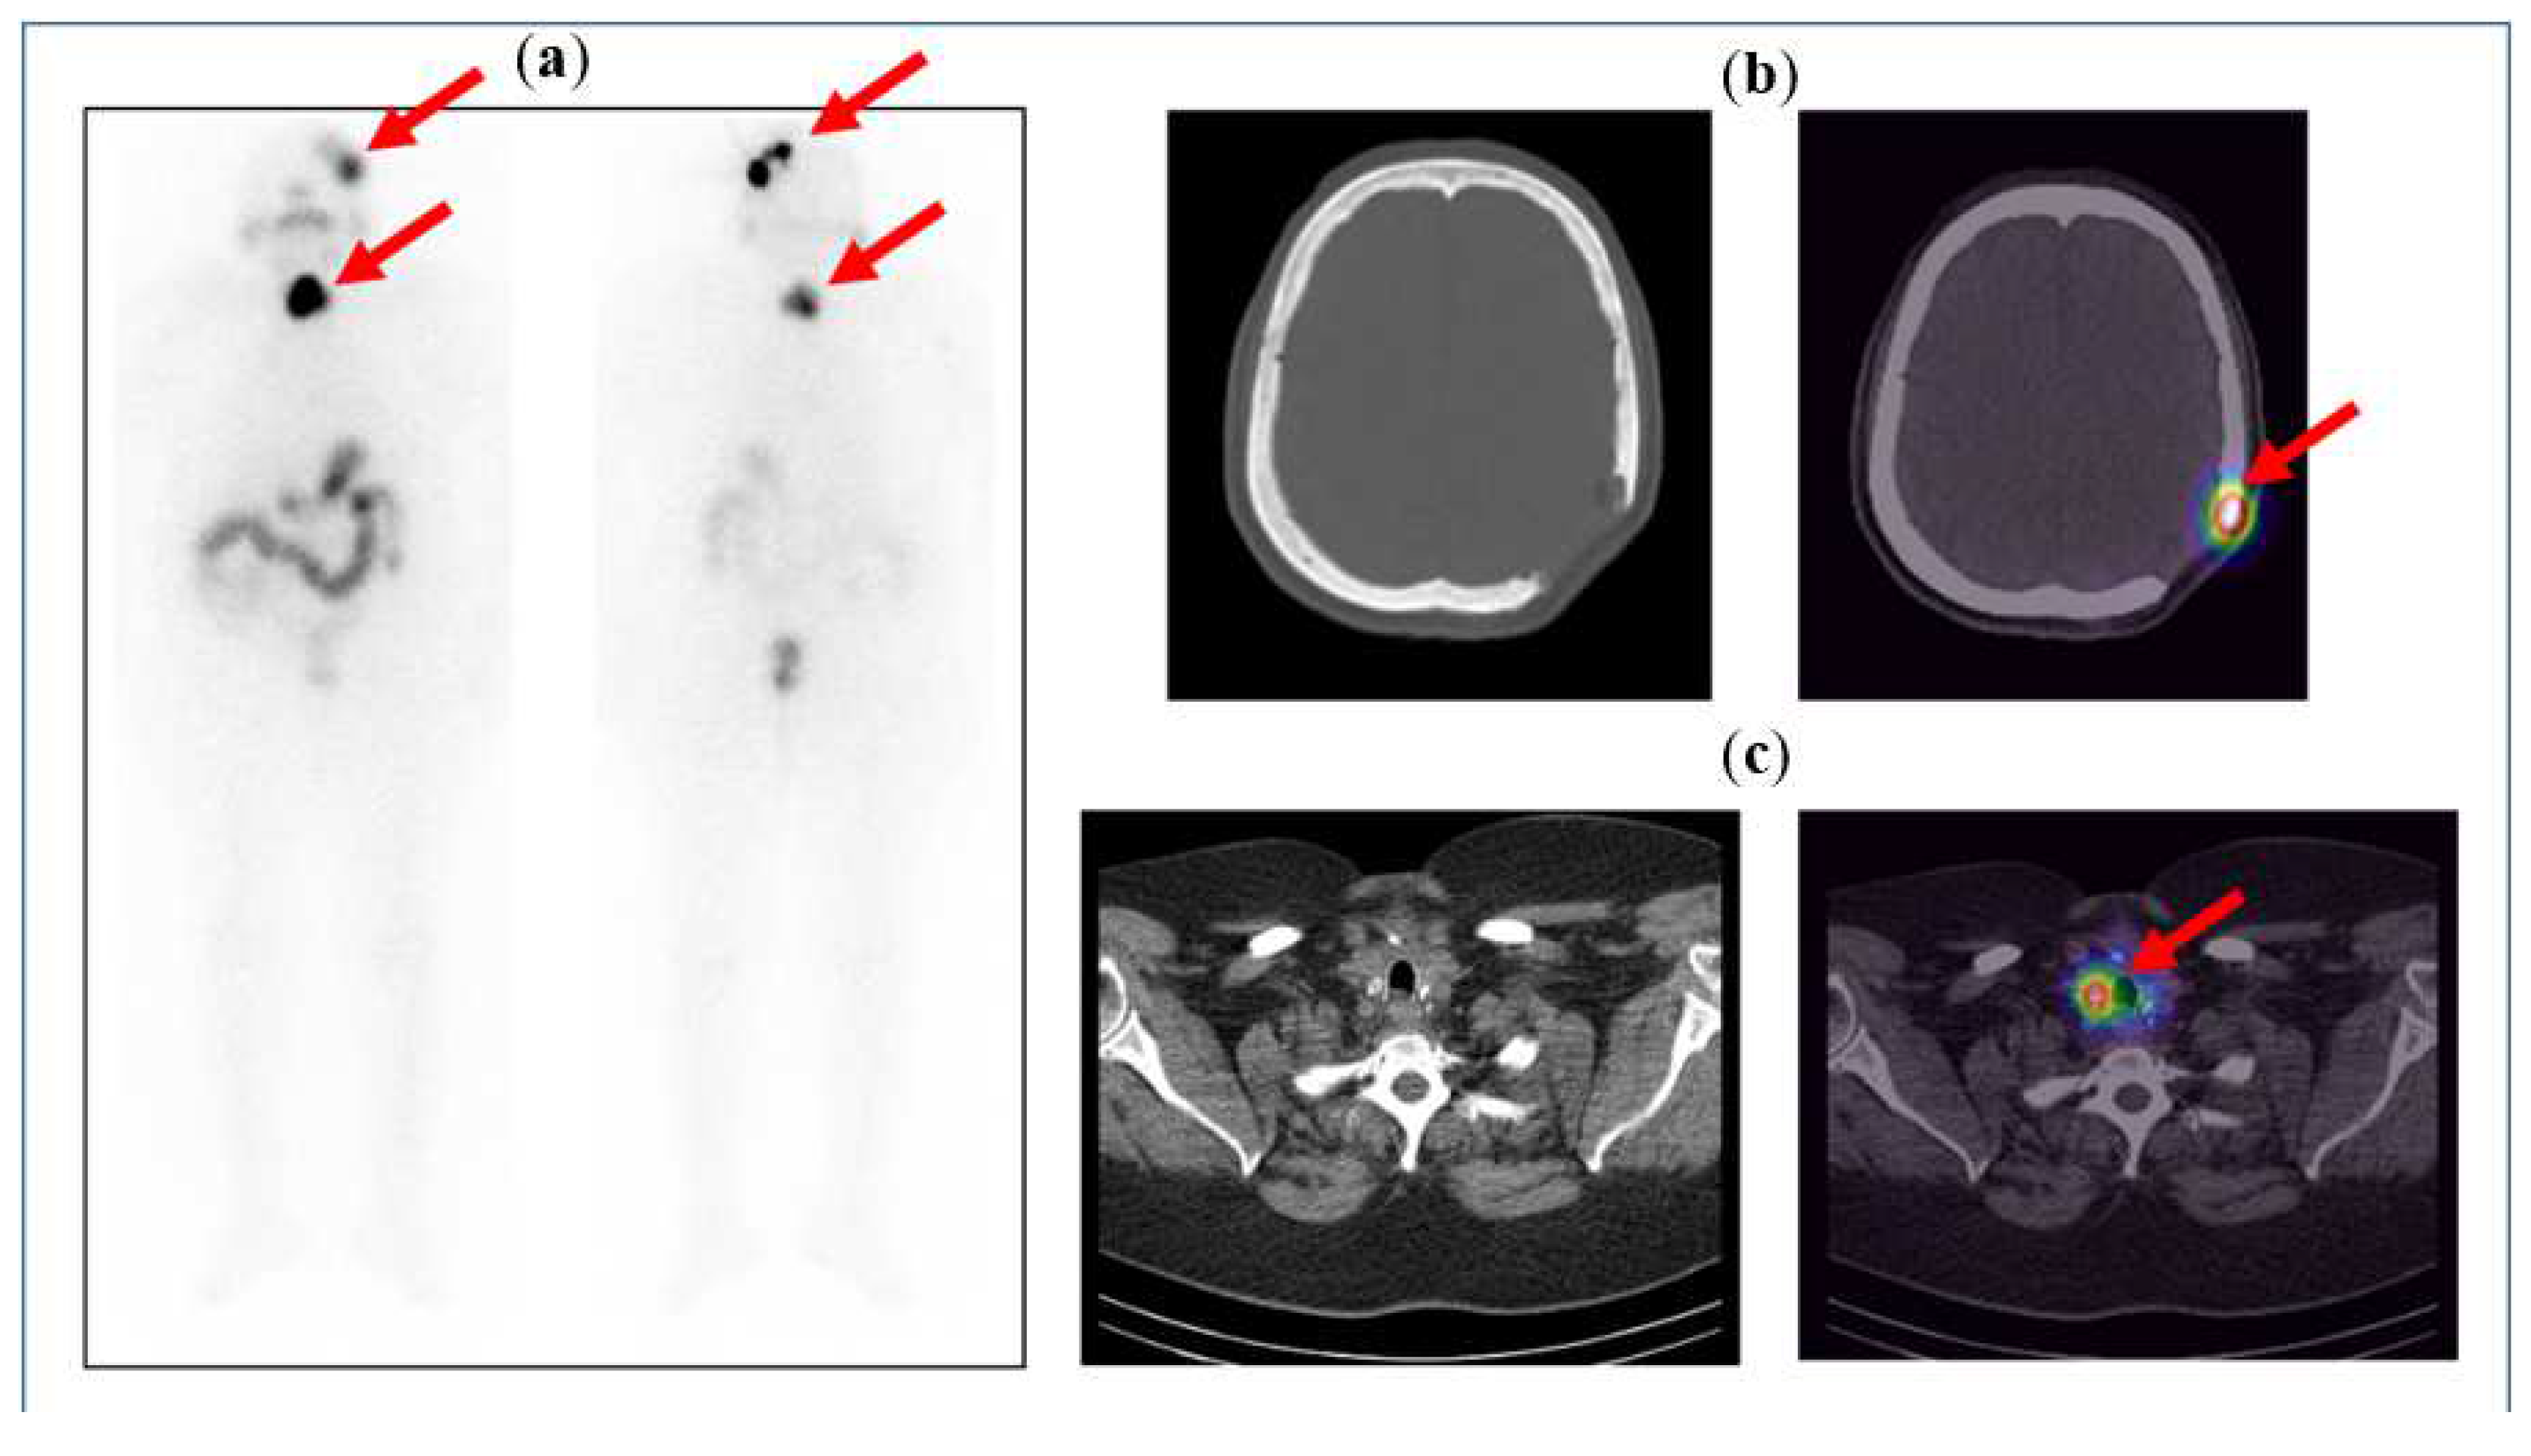

Figure 5 below illustrates the case of a 71-year-old female, known to have follicular thyroid carcinoma and skull bone metastases, after a total thyroidectomy with neck dissection and post-excision of the skull bone metastases. The patient was given a high dose of 5.5 GBq radioactive iodine (RAI) therapy, and the post-therapy scan shows iodine uptake in the neck, which is localised to the residual thyroid tissue on the SPECT/CT images, and iodine uptake in the left parietal bone, localising the residual tumour at the post-operative margins.

Figure 5.

(a) Anterior and posterior whole-body images of the post-therapy iodine scan showing iodine uptake in the neck and the left side of the skull. Physiological tracer distribution is seen in the salivary glands (as pointed out by the arrows), stomach, bowel loops, and urinary bladder. (b) CT and fused SPECT/CT images of the skull showing an osteolytic lesion with tracer uptake along the post-operative margin in the left parietal bone. (c) CT and fused SPECT/CT images of the neck clearly show tracer uptake in the residual tissue in the neck (seen as hot spots on the image on the right).